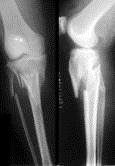

问题 病历摘要: 患者×××,男性,65岁,因车祸致伤左小腿后肿胀、活动受限、疼痛2小时。查体:左小腿上端肿胀,触痛(+),触及在骨擦音,左足伸足母、伸趾功能正常,足背动脉搏动正常。 该患者的正确诊断为: 提示: 该患者 X线片如图:

选项 A、左胫骨上段病理骨折 B、左胫骨下段粉碎性骨折 C、左胫腓骨上段粉碎性骨折 D、左胫骨中段骨折 E、左胫骨平台粉碎性骨折,左腓骨上段骨折

答案 E